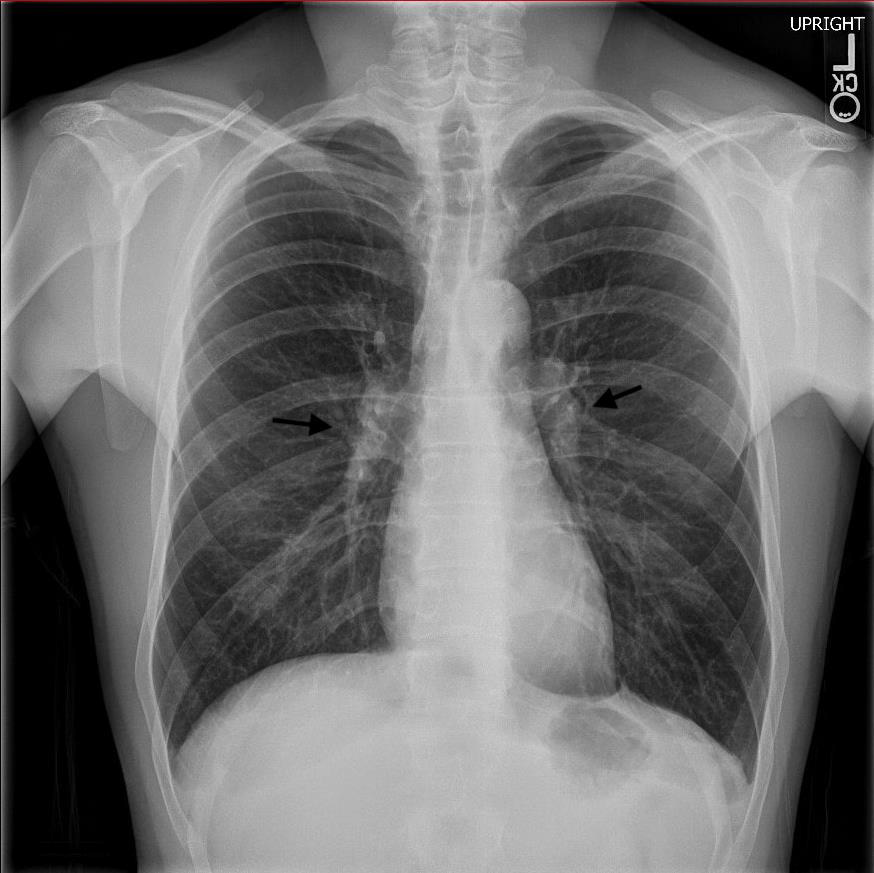

Physical exam was significant for pain with active and passive range of motion of large joints most pronounced in the right elbow, right wrist, right ankle and left knee. He had ill defined, pink erythematous patches on bilateral anterior lower extremities and 4 subcutaneous, slightly tender nodules on his upper and lower extremities. His laboratory analysis was significant for a WBC 9.52 K/cu mm (ref 3.5 - 10.8 K/cu mm) with 2% of eosinophil (ref 1-3%), creatinine of 1.32 (baseline of 1), ESR 58 mm/hr (ref 0-15 mmg/ hr), CRP 103 mg/L (ref <10 mg/L), and urine analysis without protein, blood, or WBC. Skin biopsy of the subcutaneous nodule on the left shin nodule demonstrated both sarcoidal and tuberculoid (intermittent central necrosis) granulomatous septal panniculitis without evidence of vasculitis (Figure 2). Although the presence of caseation and few eosinophils in his biopsy favored eGPA, his clinical presentation argued more for acute sarcoidosis.

Figure 2: Skin tissue biopsy of subcutaneous nodules demonstrate sarcoidal and tuberculoid granulomatous septal panniculitis.